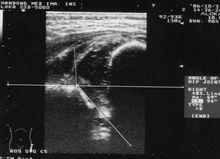

2.超聲檢查

超聲檢查有多種方法,套用最廣泛的是Graf方法。Graf方法是通過測量α角和β角,它們分別代表骨性髖臼的角度和軟骨部分的角度。根據不同的指標,髖關節被分成四型,和數個亞型。超聲檢查主要用於6個月以內嬰兒。

(1)優點 ①特異性和敏感性高,均大於90%,假陰性少;②對脫位、半脫位和髖臼發育不良都可以診斷;③可對DDH的治療進行動態觀察;④沒有放射損害。

(2)缺點 結果差異大,對檢查者要求高。

發育性髖關節發育不良超聲檢查